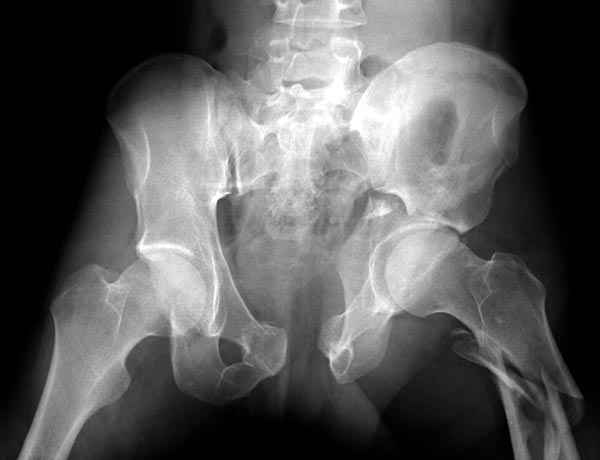

Все выступающие коллеги высказались насчет необходимости стандартных снимков по Judet, потому что для определения тактики лечения переломов вертлужной впадины 3Д снимки малоинформативны.

Летурнель разработал классификсацию на основании прямого, запирательного и подвздошного рентген снимков, котоые, кроме описания характера переломов, также подсказывают адекватный доступ для репозиции перелома.

Из того минимума, что представлено, мне кажется, мы имеем дело с двухколонным переломом вертлужной впадины. Обычно медиальный (центральный) "вывих" головки встречаются в сложных двухколонных переломах со смещением.